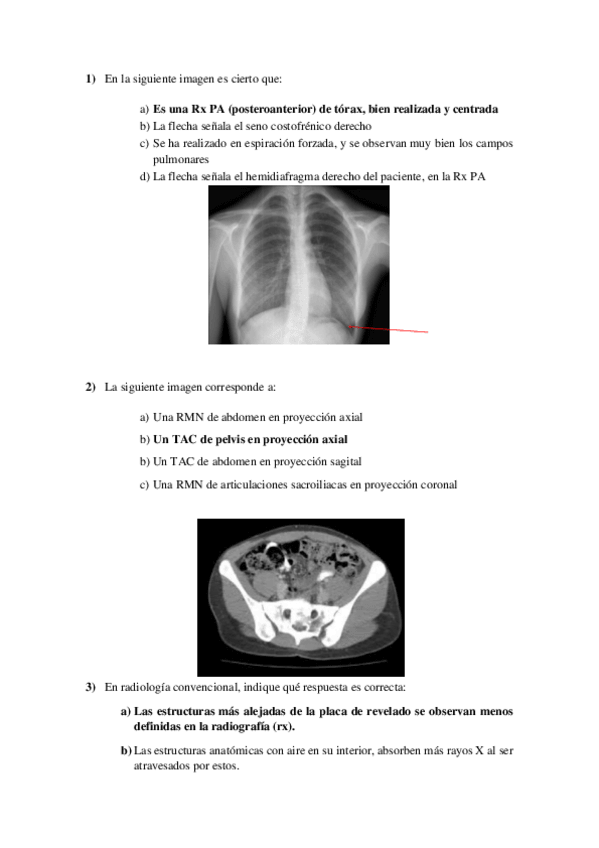

He publicado nuevos examenes de 2º Radiología en Fisioterapia: EXAMEN-RADIOLOGIA.pdf

He publicado nuevos examenes de 2º Radiología en Fisioterapia: SOLUCIONES-EXAMEN-MMSS.pdf

He publicado nuevos examenes de 2º Radiología en Fisioterapia: Examen-MMSS.pdf

He publicado nuevos examenes de 2º Radiología en Fisioterapia: MODELO-4-examen-EJERCICIO-PRACTICO-copia.pdf

He publicado nuevos examenes de 2º Radiología en Fisioterapia: MINIEXAMEN-MODELO-EJERCICIO-PRACTICO-copia.pdf